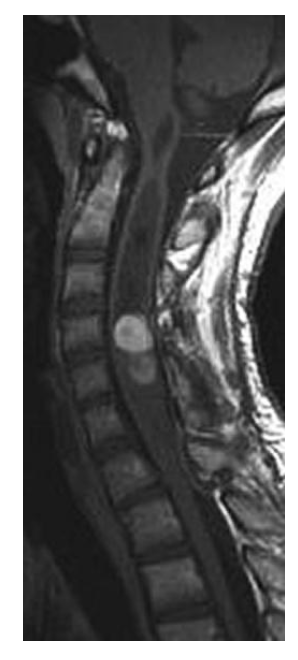

Which one of the following is most likely based on the T2-Weighted MRI shown below?

a. Ependymoma

b. Lipoma

c. Neurofibroma

d. Primary CNS lymphoma

e. Schwannoma

A

However, studies have shown that ependymomas

have a predilection for the caudal spinal cord,

with 50% of ependymomas arising in the lumbosacral cord or filum terminale and the remaining 50% occurring nonpreferentially along the cervical or thoracic spinal cord. On imaging, anaplastic ependymomas may be distinguished by their larger size, numerous cysts, and heterogeneous postcontrast enhancement. Anaplastic ependymomas are uncommon, comprising only 5% of all ependymomas, but they are characterized by anaplastic features (i.e. vascular proliferation, mitotic figures, cellular pleomorphism, and necrosis) on histologic analysis. Patients experience higher rates of tumor recurrence and decreased rates of survival. Classic radiographic features of spinal cord ependymomas include distinct tumor-spinal cord border, an associated syrinx, cysts within or adjacent to the mass, and hemosiderin deposits or “caps” near the poles of the tumor on T1 and T2. The treatment of

choice is gross total surgical resection.

A 34-year-old male presents with a several month history of neck pain, with intermittent episodes of arm and leg numbness. MRI is shown. Which one of the following is most likely?

b. Ganglioglioma

c. Meningioma

d. Neurofibroma

Ependymomas arise from ependymal cells and

typically occur in the central canal of the spinal

cord, the filum terminale, and the white matter

adjacent to a ventricular surface. They are the commonest intramedullary spinal cord tumor in adults and commoner in males than females (the commonest intramedullary tumors in children are

astrocytoma, ganglioglioma then ependymoma).

The mean age at presentation is 30-40 years with

long duration of symptoms (e.g. 2-4 years). Two

thirds occur in the lumbosacral region (40% of

these arise from the filum terminale (myxopapillary ependymoma). Because of the propensity of these tumors for seeding the craniospinal axis,

CSF evaluation and MRI of the whole craniospinal axis is strongly recommended. The three

main subsets of ependymomas are cellular (this

case), myxopapillary, and anaplastic. Cellular

ependymomas are most often located in the cervical spine. On T1-weighted MRI, they are isointense to hypointense, whereas on T2-weighted MRI, they are hyperintense and there may be a syrinx in 50% of cases. Factors prognostic for a favorable outcome include patient age younger than 40 years; tumors with a lumbosacral location, myxopapillary histologic findings, or a grade of WHO grade I; tumors amenable to GTR or

STR; and good preoperative function of the

patient. Whether volume of residual disease

correlates with a worse outcome after EBRT is

controversial. Most intradural extramedullary

ependymomas are myxopapillary and are often

amenable to complete surgical resection if they

are not multifocal. The goal of surgery is GTR.

Every attempt should be made to remove tumors

as a whole as opposed to piecemeal removal,

because of the risk of seeding, including upward

seeding to the cranial nerves. Typically, complete

resection is achievable in 80-100% of modern

series, with 10-year survival for all spinal cord

ependymomas is 70-100%. Postoperative EBRT

appears to improve local control in patients with

STR ependymomas and also for patients with

high-grade lesions and those with neuraxis dissemination. In most but not all series, the outcome for STR followed by EBRT appears to be

similar to that of complete resection. In patients

with tumors at high risk of seeding, when pretreatment CSF cytologic studies reveal malignant cells, or if the spinal MRI scan shows evidence of leptomeningeal disease, the craniospinal axis should be

treated. There is no strong body of evidence

thus far demonstrating that the addition of

chemotherapy to EBRT improves the outcome,

but it is used in pediatric patients with anaplastic

ependymoma or ependymoblastoma are routinely

given chemotherapy